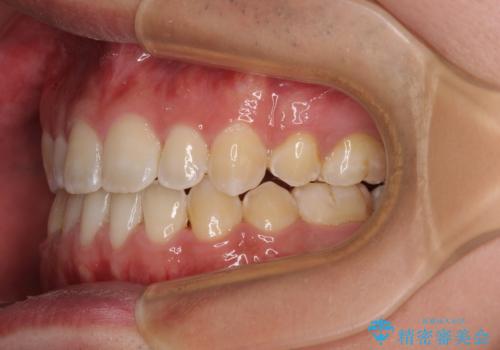

- 受け口傾向の咬み合わせと口元の突出感を気にして来院された患者様です。

受け口傾向特有の狭い上顎歯列であったため、歯列の拡大を補助装置で行い、下顎歯列全体を後方に移動させることとしました。

奥歯の咬み合わせを改善させた後、上下左右の小臼歯(下顎は残存乳歯)を計4本抜歯し、ワイヤー装置にて口元の突出感を改善しながら咬み合わせを整えることとしました。

下顎の残存乳歯は小臼歯よりも大きいため、スペースを閉じるために長い期間を必要としますが、予想通りに長期間を要することとなりました。

受け口傾向の方の抜歯矯正は、下顎前歯が舌側に倒れることで歯肉退縮を起こしやすいことが知られていますが、ワイヤーに工夫をすることでリスクを軽減させています。